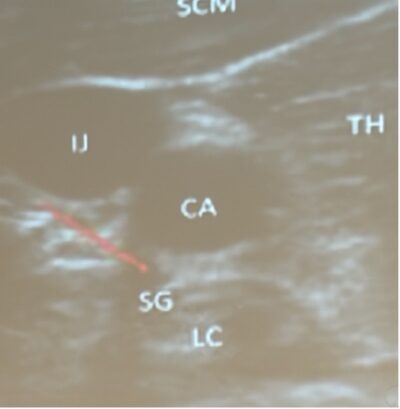

- Stellate Ganglion block is a fairly simple procedure using PoCUS similar to placing a central line.

Stellate Ganglion Block Procedure

- Indication: refractory VF / suspected electrical storm physiology after optimized defibrillation strategy and standard meds

- Do not stop CPR: perform during ongoing chest compressions whenever feasable

- Use ultrasound guidance

- Identify left carotid artery

- Target location: just inferior to the left carotid at roughly the 6 o’clock position, typically around C6

- Injectate: ~20 mL lidocaine or bupivacaine into the appropriate fascial plane adjacent to the stellate ganglion under ultrasound visualization

- Goal: reduce sympathetic tone and ventricular irritability; suppress recurrent VF